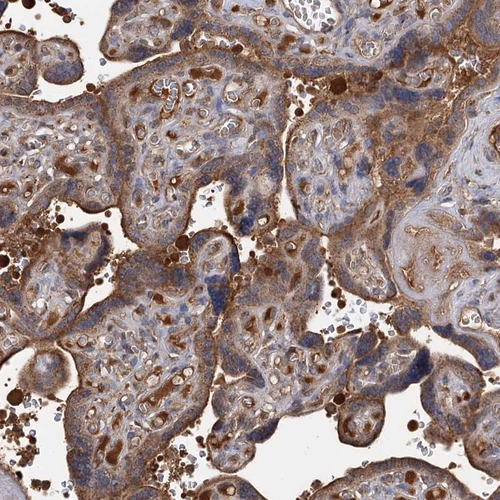

Immunohistochemical staining of human testis shows strong cytoplasmic positivity in Leydig cells.